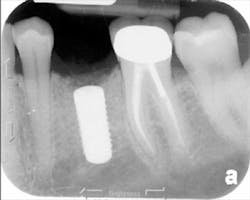

The patient was seen four months later for Stage II uncovering of her implant using a tissue punch and was sent to her restorative dentist for final impressions two weeks after that. Three months after the initial surgery, the patient returned with her final restoration in place for a soft-tissue exam and radiograph. Six months after surgery, she returned for a postdelivery radiograph, shown here. (I see every implant patient three months after seating the final restoration to check for residual cement, ensure that the restorative apparatus is fully seated, and check the soft- and hard-tissue response to the new restoration. This is an extremely important—and often overlooked visit—where problems are often noted that can cause significant damage to the bone and gingiva if early intervention is not initiated.) The bone levels were well-maintained around the implant platform, and the soft-tissue health was excellent. The patient reported a high degree of satisfaction with her new implant restoration.

The patient returned three and six months later for a postdelivery radiograph and healing check. The peri-implant tissues were healthy with no abnormal bleeding or probings. The patient reported high satisfaction with his new implant restoration.